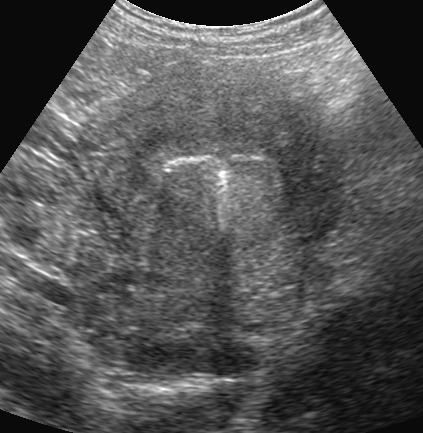

Utérus en coupe frontale. DIU en place (Cliché : Dr. C. TALMAN).